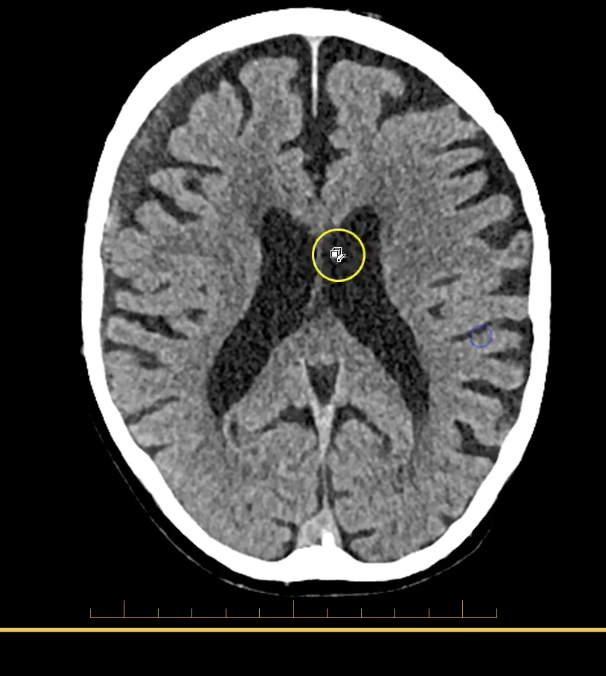

term image

lateral ventricles